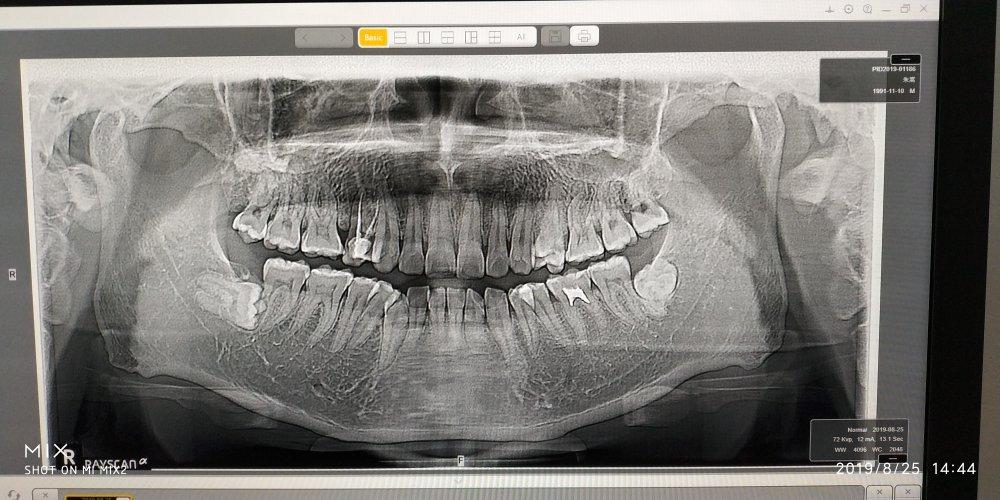

补牙拍片多久可以怀孕

补牙是一件非常麻烦的事情,因为要涉及到部分药物,同时还会影响正常的进食,补牙的方法也有很多种,但是对于在备孕期间的孕妈妈来说,补牙的问题一直是非常重要的。那么,补牙拍片多久可以怀孕呢?